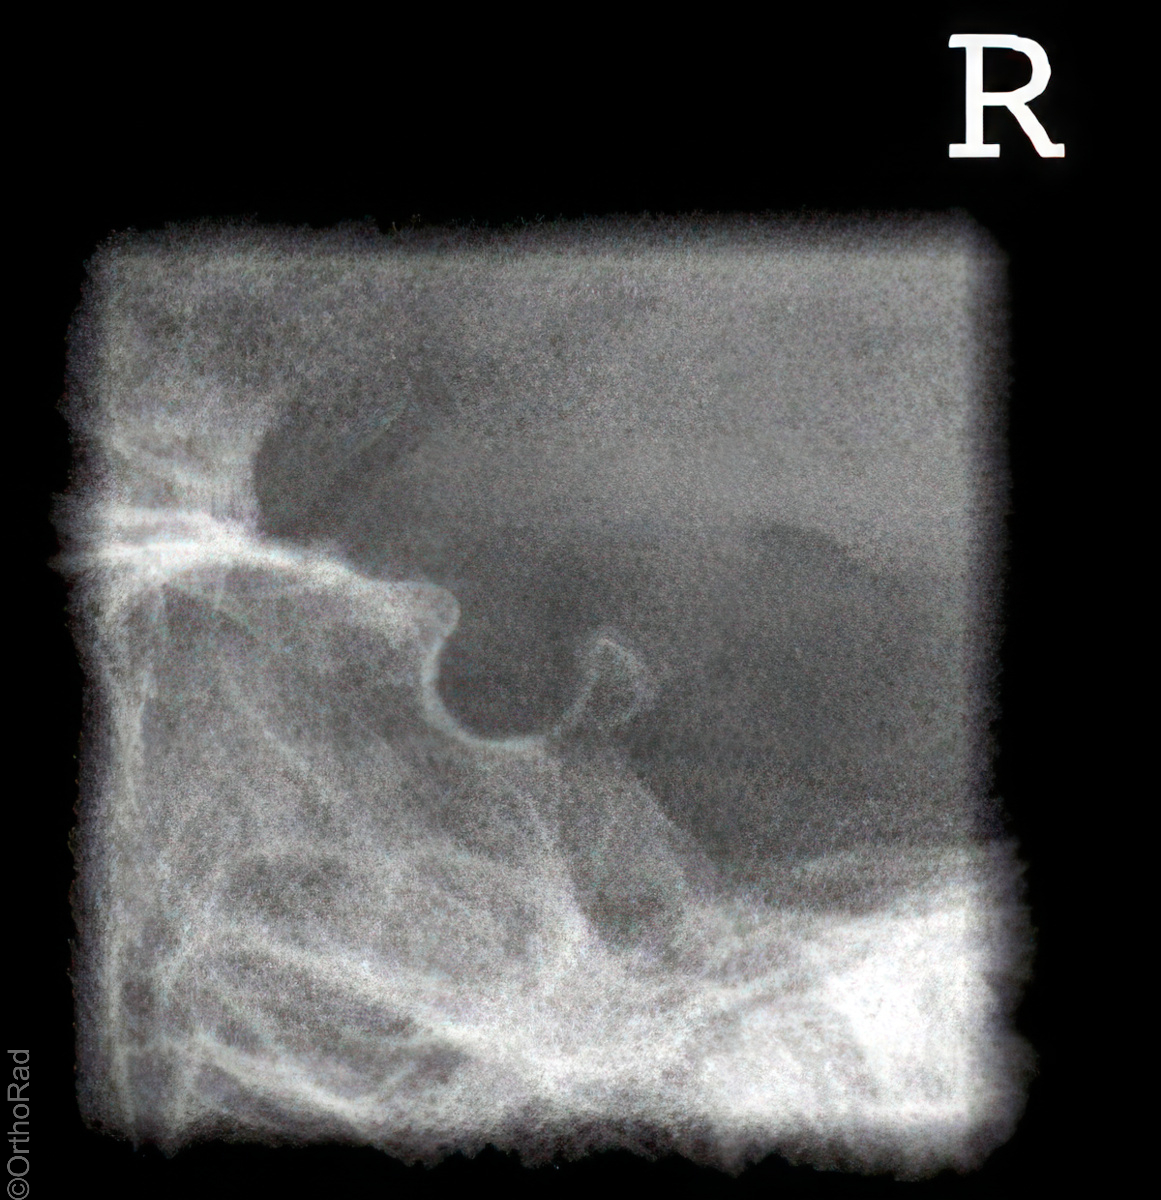

Kieferköpfchen nach Schüller

Technik

• FDA: 1,15 m

• Ausgangsformat: 18/18

• mit Raster

• Röhrenkippung: 20° cranio-caudal

Lagerung

Bauchlage, d.h. stabile Seitenlage, wie Schädel seitlich

zu untersuchende Seite aufliegend

Zentralstrahl

Zielt mit ca. 20° cranio-caudal auf das aufliegende Ohr (Zur Hilfe kann das detektorferne Ohr verwendet werden, welches auf die Platte projiziert wird.)

Qualitätskriterien

Freier Einblick auf das Kiefergelenk.